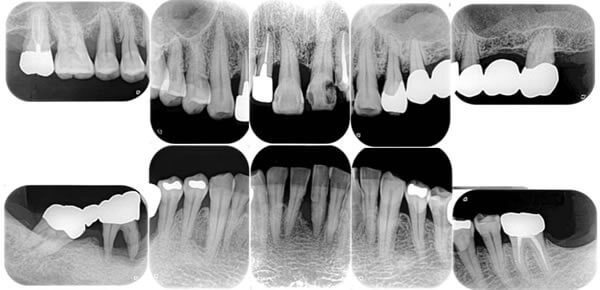

初診時の状態

(口腔内写真とデンタルX線)

症例 症例

部分的に重度に⻭周病が進行しておりレントゲン診査で左上奥⻭や左下犬⻭は、根尖部まで骨が吸収し右下奥⻭は⻭根⻑の2/3程度まで吸収しています。